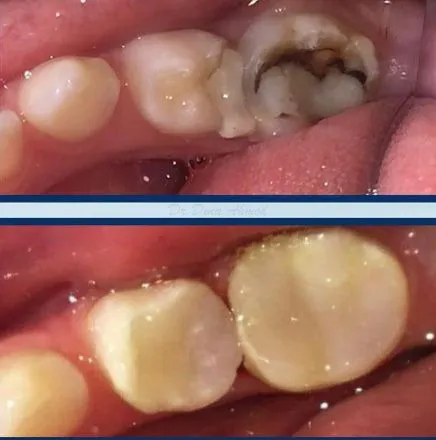

Full Mouth White Fillings

White Fillings